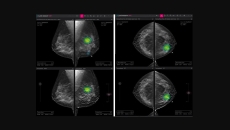

Alexander Ihls, business development manager at Healthcare DACH, InterSystems, discusses how radiologists are benefiting from artificial intelligence.